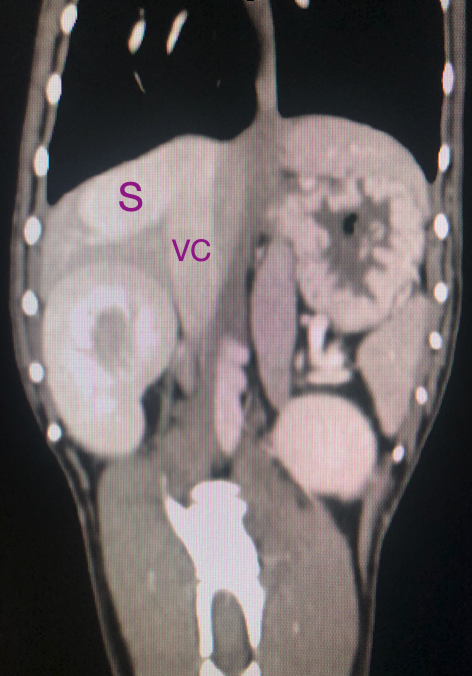

The Interventional Radiology (IR) team closing an abnormal blood vessel (S) in the liver of a dog draining into a large vein (VC). Multiple metal coils will close the vessel and return the dog's liver to normal! #weareAURA #portosystemicshunt @IRHorton @BSIR_News @IN_publishing